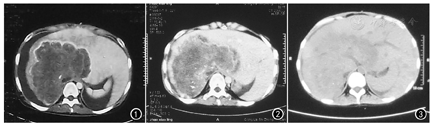

患者女,21岁。2015年5月8日,因"上腹部不适1年,发现肝脏占位15 d"到四川大学华西医院就诊。体格检查可见腹部膨隆,余无异常。Karnofsky功能状态(Karnofsky performance status, KPS)评分为70分。CT示,肝右叶巨大占位病变伴腹膜后淋巴结转移,大量腹水。行CT引导下肝脏占位穿刺活检术。病理学检查镜下见纤维化背景中少量异型腺体,未见肝组织。免疫组化染色,异型腺体广谱细胞角蛋白(pan cytokeratin, PCK)(+),组织蛋白酶K抑制剂(catheptin K inhibiters, CKIS)(+),CD10(部分+),Hepa(-),癌胚抗原(carcino-embryonic antigen, CEA)(部分+),EB病毒编码RNA1/2(EBV-encoded RNA1/2, EBER1/2)原位杂交(-)。病理诊断:高分化胆管细胞癌。5月20日行肝动脉化疗栓塞术。出院后,患者临床症状无明显好转,肝功能损伤加重,腹水增加,每天达2 000~3 000 ml。2015年6月29日再次入住四川大学华西医院。7月6日行CT引导肝穿刺无水酒精注射治疗术和肝动脉灌注化疗栓塞术。7月10日病情稳定后出院。出院后,患者肝功能损伤加重,腹水持续增加。9月25日,患者因出现厌油、恶心呕吐、纳差、慢性顽固性疼痛、严重营养不良、贫血、低蛋白血症及电解质紊乱,到成都市西区医院就诊。入院查体:患者精神差,面色苍白,少尿,腹壁紧张并静脉曲张。KPS评分为50分。腹水中发现肿瘤细胞。CT示,肝右叶及肝左叶内侧段大片低密度影,腔静脉局部可见充盈缺损,腹腔大量积液(图1)。入院后多次给予顺铂20 mg腹腔灌注化疗及保肝、止痛等对症治疗。11月19日出院。

由于病情日益恶化,患者于2016年1月20日入住我院。体格检查:患者神志清楚,精神差,说话语音微弱,行走困难。进食差,消瘦,体重40 kg。面色和眼睑苍白,皮肤及巩膜无黄染。少尿,蛙状腹,腹壁静脉曲张,腹部叩诊呈移动性浊音。双侧留置腹腔引流管,腹水色黄,引流量每天3 000~4 000 ml。KPS评分为20分。患者签署知情同意书后,2016年1月20日开始肿瘤声动力治疗。皮试确认阴性后,将血卟啉注射液按5 mg/kg体重的剂量避光静脉输入,避光24 h后,经超声波定位,使用XK-2011R肿瘤超声波治疗仪(武汉兴康医疗器械有限责任公司产品)对整个肝脏和肝门血管进行3D全方位声动力治疗。声频450 kHz,声强1.5 W/cm2。每次30 min,2次/d,连续3 d为1个周期。共治疗6个周期,每两个周期之间间隔3个月。每周期治疗结束后,患者避免阳光照射30 d。在第1个周期声动力治疗后2周,患者腹水引流量减少至每天1 500 ml左右。食欲明显恢复,体重增加,尿量正常。首次声动力治疗后第3个月门诊复查,患者精神良好,面色红润,皮肤、巩膜无黄染,腹壁无静脉曲张,腹软,肝脏未触及,脾脏肋缘下一指。腹腔引流管通畅,腹水色淡黄,引流量每天500 ml。KPS评分为90分。术后7个月CT检查示,肝脏增大,肝叶比例正常,肝裂无增宽,肝表面光滑。肝右叶见大片状低密度影,边界不清,密度不均匀。脾脏增大,门静脉及下腔静脉无增宽,腹膜后未见明显肿大淋巴结,腹腔内无积液(图2)。第16个月CT检查示,右肝叶占位密度明显减低,接近正常肝组织。肝左叶代偿性增大。脾脏增大,门静脉及下腔静脉无增宽,腹腔内无积液(图3)。为证实声动力治疗的疗效,2017年7月6日患者在四川省肿瘤医院局麻下行CT引导下肝脏占位穿刺活检术。病理检查未见肿瘤细胞(图4)。患者发病后出现闭经,首次声动力治疗后16个月月经周期恢复。患者至今未见复发转移,仍存活。